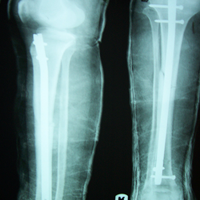

Case:8 Polytrauma

Patient having closed segmented fracture midshaft & lower 1/3 Tibia with closed fracture superior & inferior pubic rami right side with pelvis fracture following vehicular accident wastreated with intramedullary nail for fracture tibia and external fixator for fracture pelvis.

Pre-Op

Immdiate Post-op

Post-op Lateral